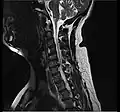

Click images to see larger versions

• Magnetic resonance imaging is the gold standard study for confirming a suspected LDH. With a diagnostic accuracy of 97%, it is the most sensitive study to visualize a herniated disc due to its significant ability in soft tissue visualization. MRI also has higher inter-observer reliability than other imaging modalities. It suggests disc herniation when it shows an increased T2-weighted signal at the posterior 10% of the disc. Degenerative disc diseases have shown a correlation with Modic type 1 changes. When evaluating for postoperative lumbar radiculopathies, the recommendation is that the MRI is performed with contrast unless otherwise contraindicated. MRI is more effective than CT in distinguishing inflammatory, malignant, or inflammatory etiologies of LDH. It is indicated relatively early in the course of evaluation (<8 weeks) when the patient presents with relative indications like significant pain, neurological motor deficits, and cauda equina syndrome. Diffusion tensor imaging is a type of MRI sequence used for detecting microstructural changes in the nerve root. It may be beneficial in understanding the changes that occur after herniated lumbar disc compresses a nerve root, and might help in differentiating the patients that need surgical intervention. In patients with a high suspicion of radiculopathy due to lumbar disc herniation, yet the MRI is equivocal or negative, nerve conduction studies are indicated.[44] T2-weighted images allow for clear visualization of protruded disc material in the spinal canal.